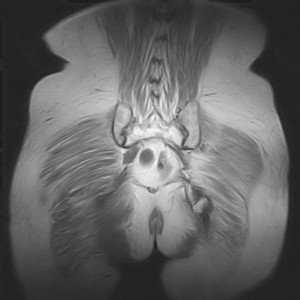

图像太差了 1、右侧臀肌旁脓肿? 建议增强 2、左侧股骨头坏死并半脱位

1、左侧股骨头坏死并髋关节半脱位;

2、右侧臀肌感染,(可能褥疮所致)